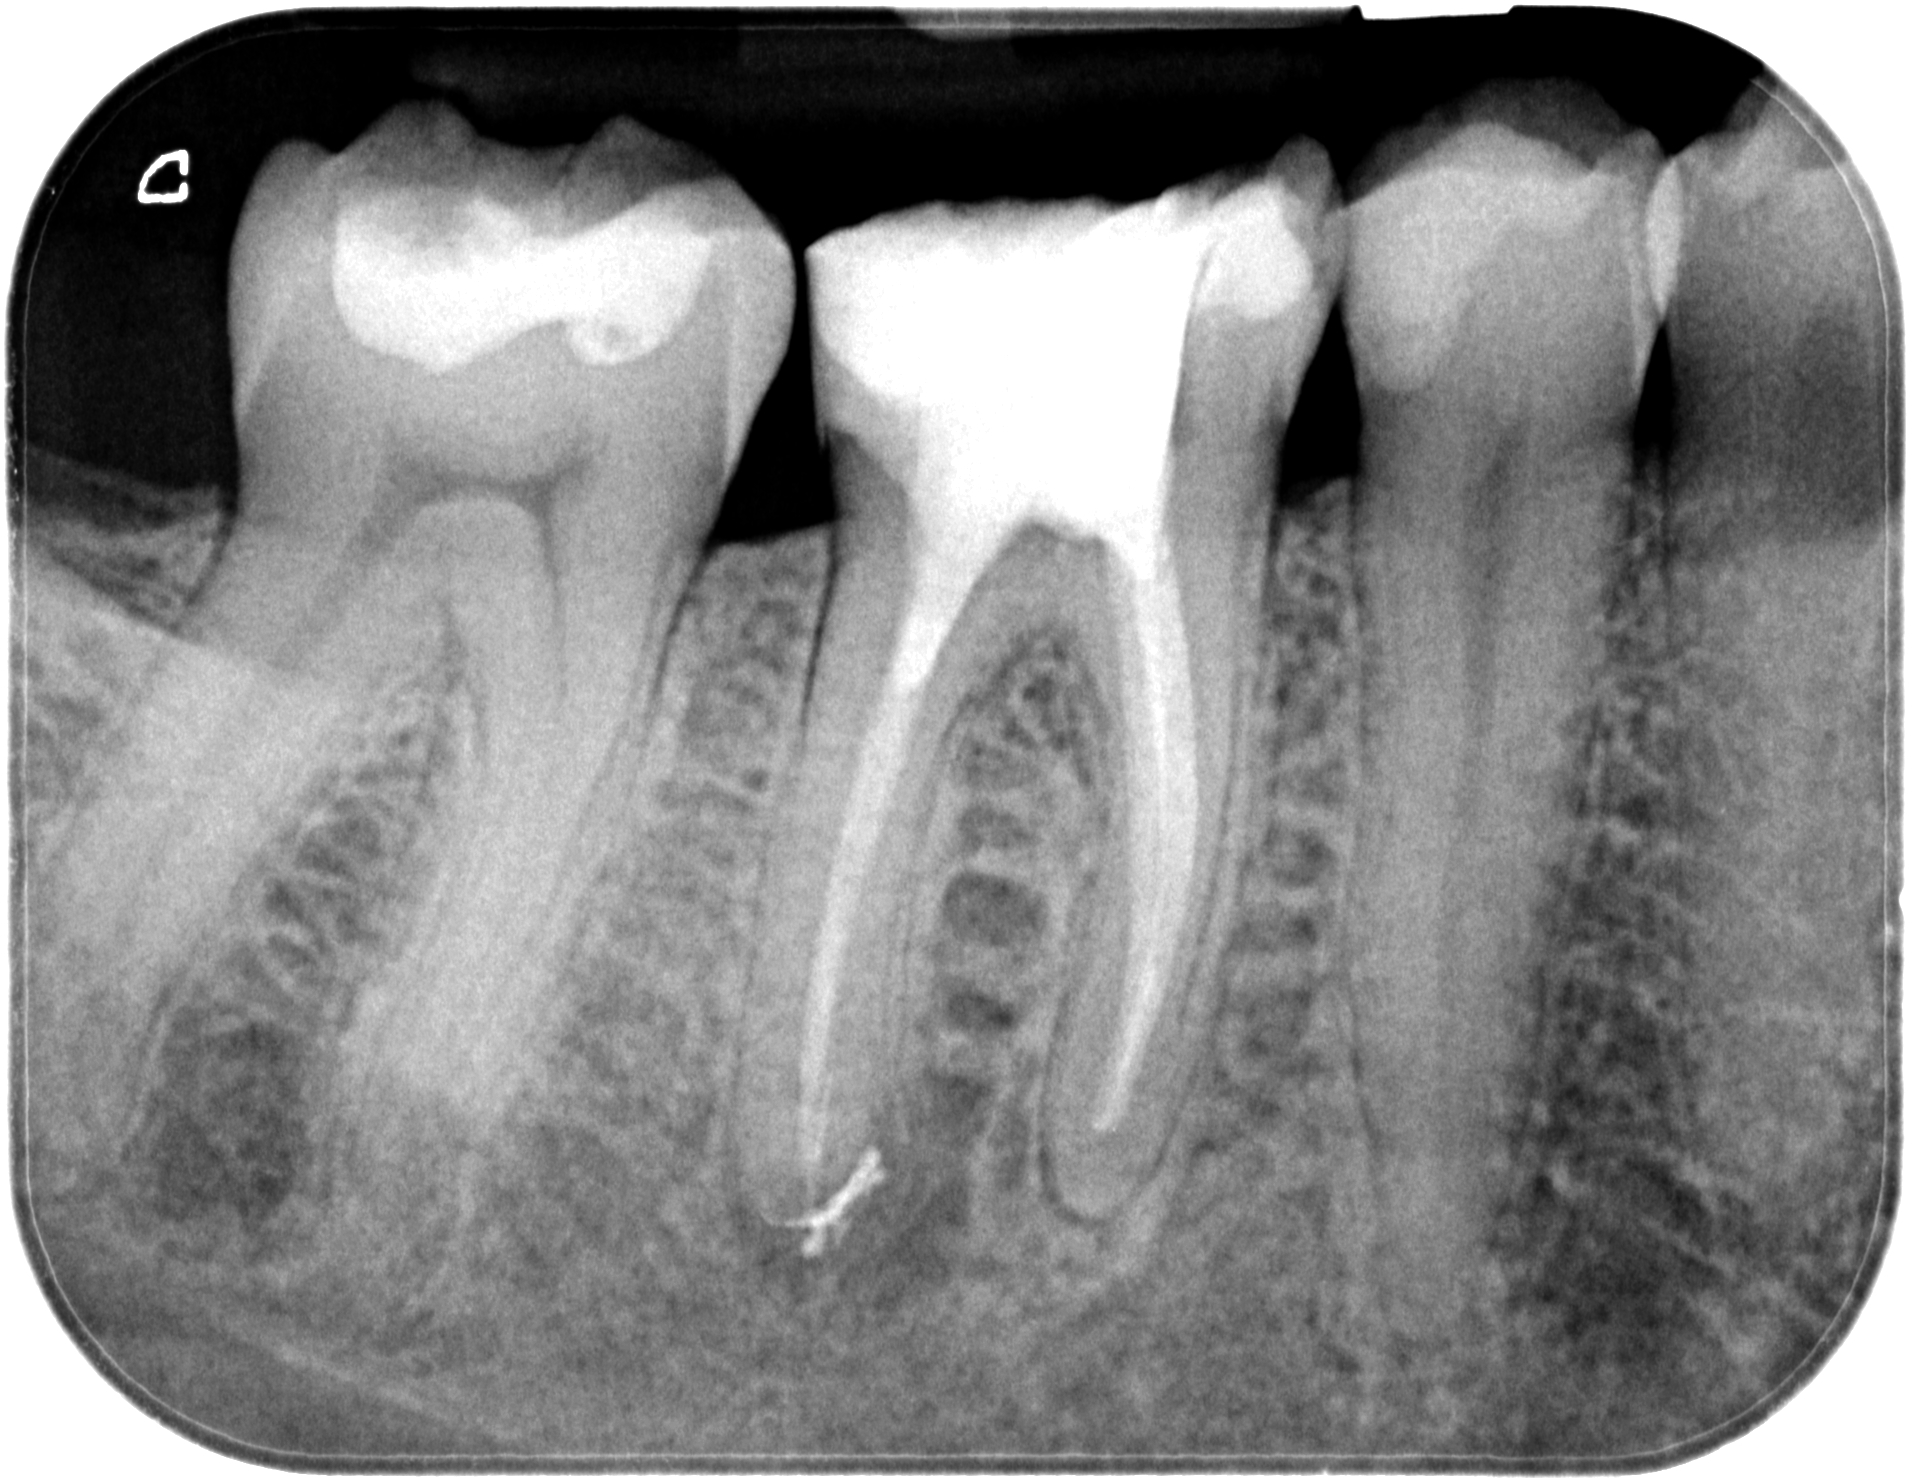

02.03.2020 Patientin DW, geb. am 12.04.1968, Zahn 46, WF Revision, WF-Kontrolle 7 Monate post WF